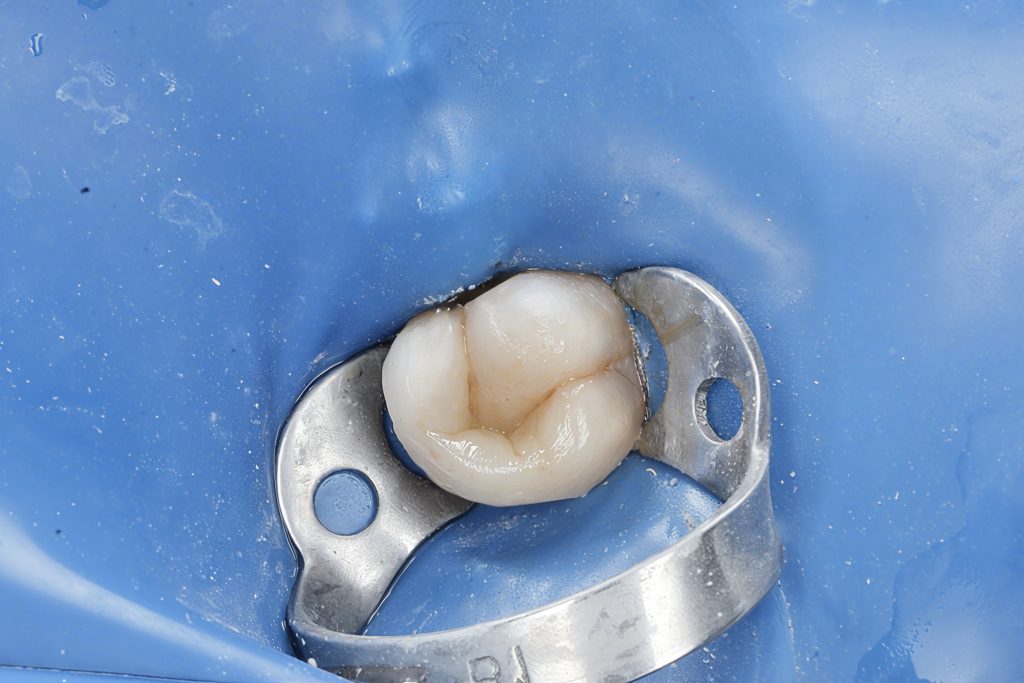

D. Cuspal Coverage Restoration

Given the structural loss, cuspal reinforcement was mandatory.

Composite Onlay-Style Build-Up

- Adhesive: Universal adhesive with selective enamel etching

- Dentin replacement: High-strength composite

- Enamel layer: Esthetic nano-hybrid composite with anatomical layering

- Functional morphology sculpted under microscope

Why composite cuspal coverage?

- Superior stress distribution

- Biomimetic modulus of elasticity close to dentin

- Tooth preservation vs. full crown prep

- Less chair time and lower biological cost

E. Post-Operative Evaluation

Clinical outcomes

✔ Excellent marginal integrity

✔ Healthy gingival response

✔ Proper occlusal contacts and harmony

✔ Smooth transition from tooth to composite

✔ Anatomical fissures and functional cusps maintained